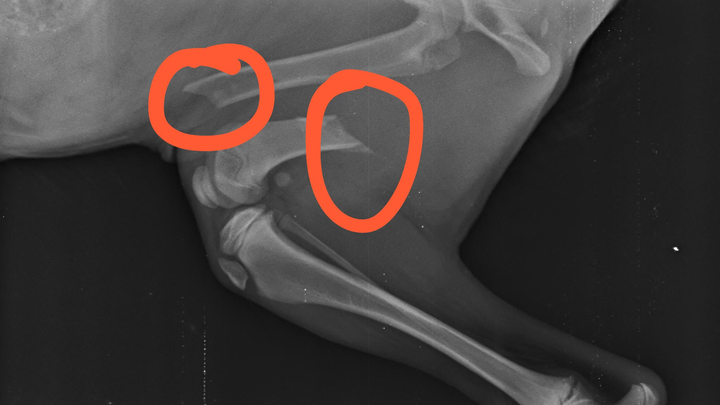

Hi I am Lisa and I am trying to raise funds to help pay for vet treatment for this puppy who was found on the side of the road with 2 broken legs. Poor little thing is a stray and needs our help.